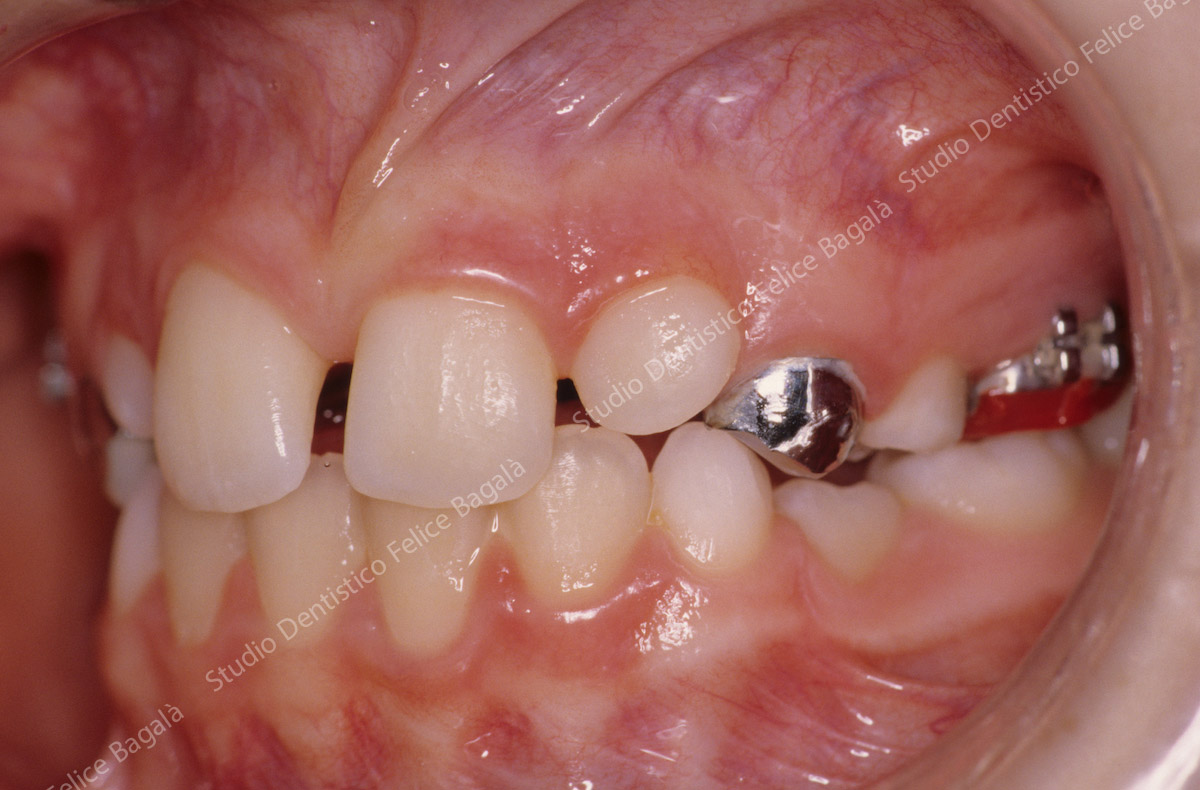

IL CASO DI DANIELE (MORSO CROCIATO)

Daniele 8 anni Morso crociato destro con deviazione mandibolare  e linee mediane dallo stesso lato (vedi frecce nere). Dopo allargamento della parte superiore (mascellare e palato) la mandibola si porta al centro (vedi frecce nere) . Daniele da quel momento continuerà a crescere e sarà controllato periodicamente. Dopo questo breve fase intercettiva di durata di 8/10 mesi non ha avuto più alcun bisogno di ortodonzia. Le deviazioni mandibolari da morso crociato vengono annoverate tra i principali motivi di disturbi muscolo articolari ( Disfunzioni ATM) nell’adulto.

Durante